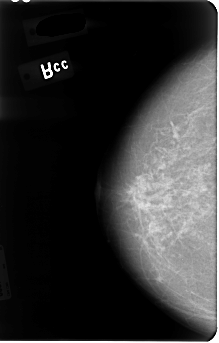

B_3046_1.RIGHT_CC

RIGHT_CC LINES 4792 PIXELS_PER_LINE 3056 BITS_PER_PIXEL 12 RESOLUTION 50 NON_OVERLAY